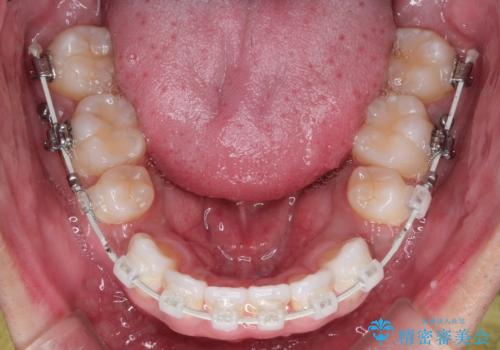

前歯の突出を防ぎながらガタつきを解消。上下左右4番抜歯による審美ワイヤー矯正

非抜歯で無理に並べようとすると、歯列が外側に広がり、前歯が前方に突き出て口元が突出してしまうリスクがありました。患者様の「これ以上前歯を外に出したくない」という強いご希望を重視し、上下左右の4番目の歯(第一小臼歯)を計4本抜歯してスペースを確保する計画を立案。装置は、装置の見た目を考慮し、白く目立ちにくい審美ワイヤーを選択しました。

抜歯によって作られたスペースを利用し、前歯を後方に維持したまま、ガタついている歯を一つひとつ正しい位置へと整列させていきました。

審美ワイヤーを用いることで、歯の根元から角度を精密にコントロールし、前歯が前方に傾斜するのを防ぎながらスペースを閉じていきました。これにより、口元のボリュームを維持したまま、美しいアーチ状の歯並びを構築することが可能となりました。